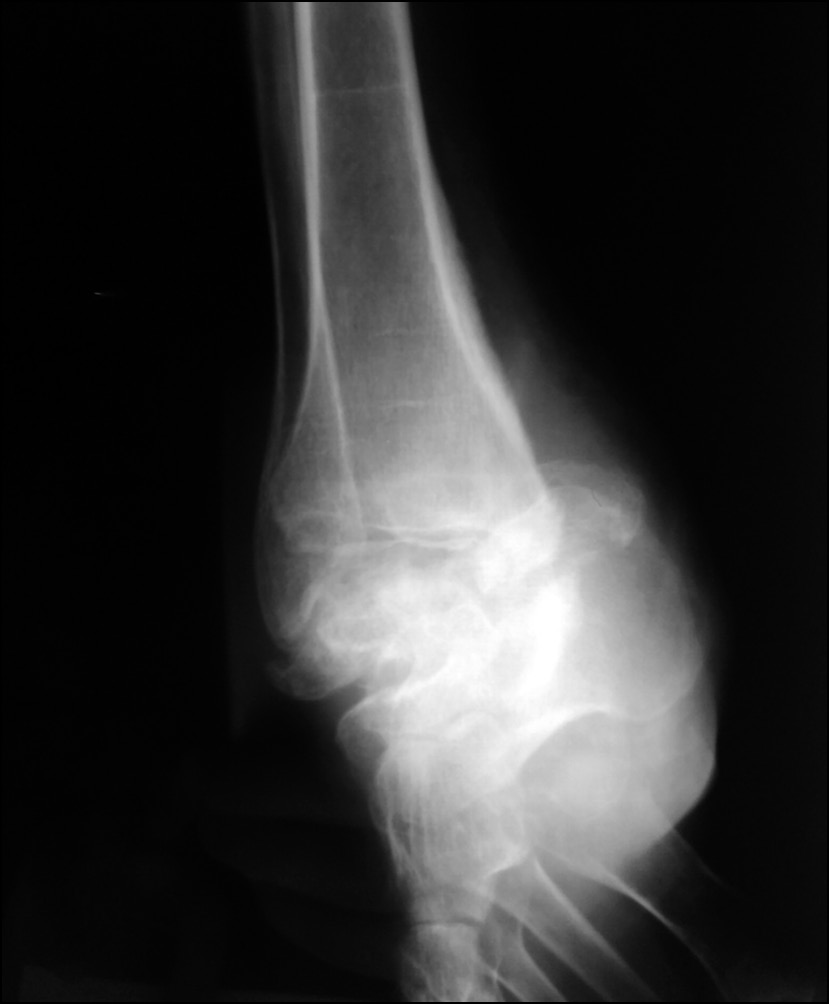

Рентгенологически выявлен спиралевидный перелом метафизарной зоны большеберцовой кости со смещением на стадии консолидации с образованием объёмной костной мозоли. Как и ранее, отмечались признаки снижения МПКТ (рис. 7, 8).

Рис. 7. Рентгенограмма в передне-задней проекции.

Fig. 7. X-ray image in anterior-posterior projection.

На момент повторного поступления в стационар отмечен дефицит 25-OH витамина D — 18 нг/мг (30–100) на фоне хронической болезни почек (ХБП), С3а (скорость клубочковой фильтрации — 49 мл/мин/1,73 м2), нормального уровня кальция, скорректированного на альбумин, фосфора, что сопровождалось гиперпаратиреозом (паратиреоидный гормон — 106,8 пг/мл (15–65)). По результатам двухэнергетической рентгеновской абсорбциометрии (денситометрии) МПКТ в проксимальном отделе бедренной кости выявлена остеопения до -2 SD по Z-score, до -1,7 SD в поясничном отделе позвоночника, остеопороз до -3,0 SD в лучевой кости.

Рис. 8. Рентгенограмма в боковой проекции.

Fig. 8. X-ray image in lateral projection.

При исследовании маркеров костной резорбции и костеобразования выявлено следующее. Остеокальцин — маркер костеобразования (витамин К- и витамин D-зависимый белок, присутствует в костной и зубной ткани, синтезируется остеобластами и одонтобластами, большая часть образующегося остеокальцина откладывается во внеклеточном матриксе кости, подвергается минерализации в процессе формирования новой костной ткани, оставшаяся часть белка (10–40%) поступает в кровоток) — находился в референсном диапазоне 20,53 нг/мл (14–42), С-концевой телопептид коллагена I типа (наиболее значимый продукт деградации коллагена: в процессе резорбции остеокластами телопептиды высвобождаются в кровоток и выводятся почками) у пациентки с переломом составил 0,438 нг/мл (0,1–0,85).

На основании клинико-анамнестических данных сделан вывод о патологическом характере перелома, рекомендовано хирургическое лечение.